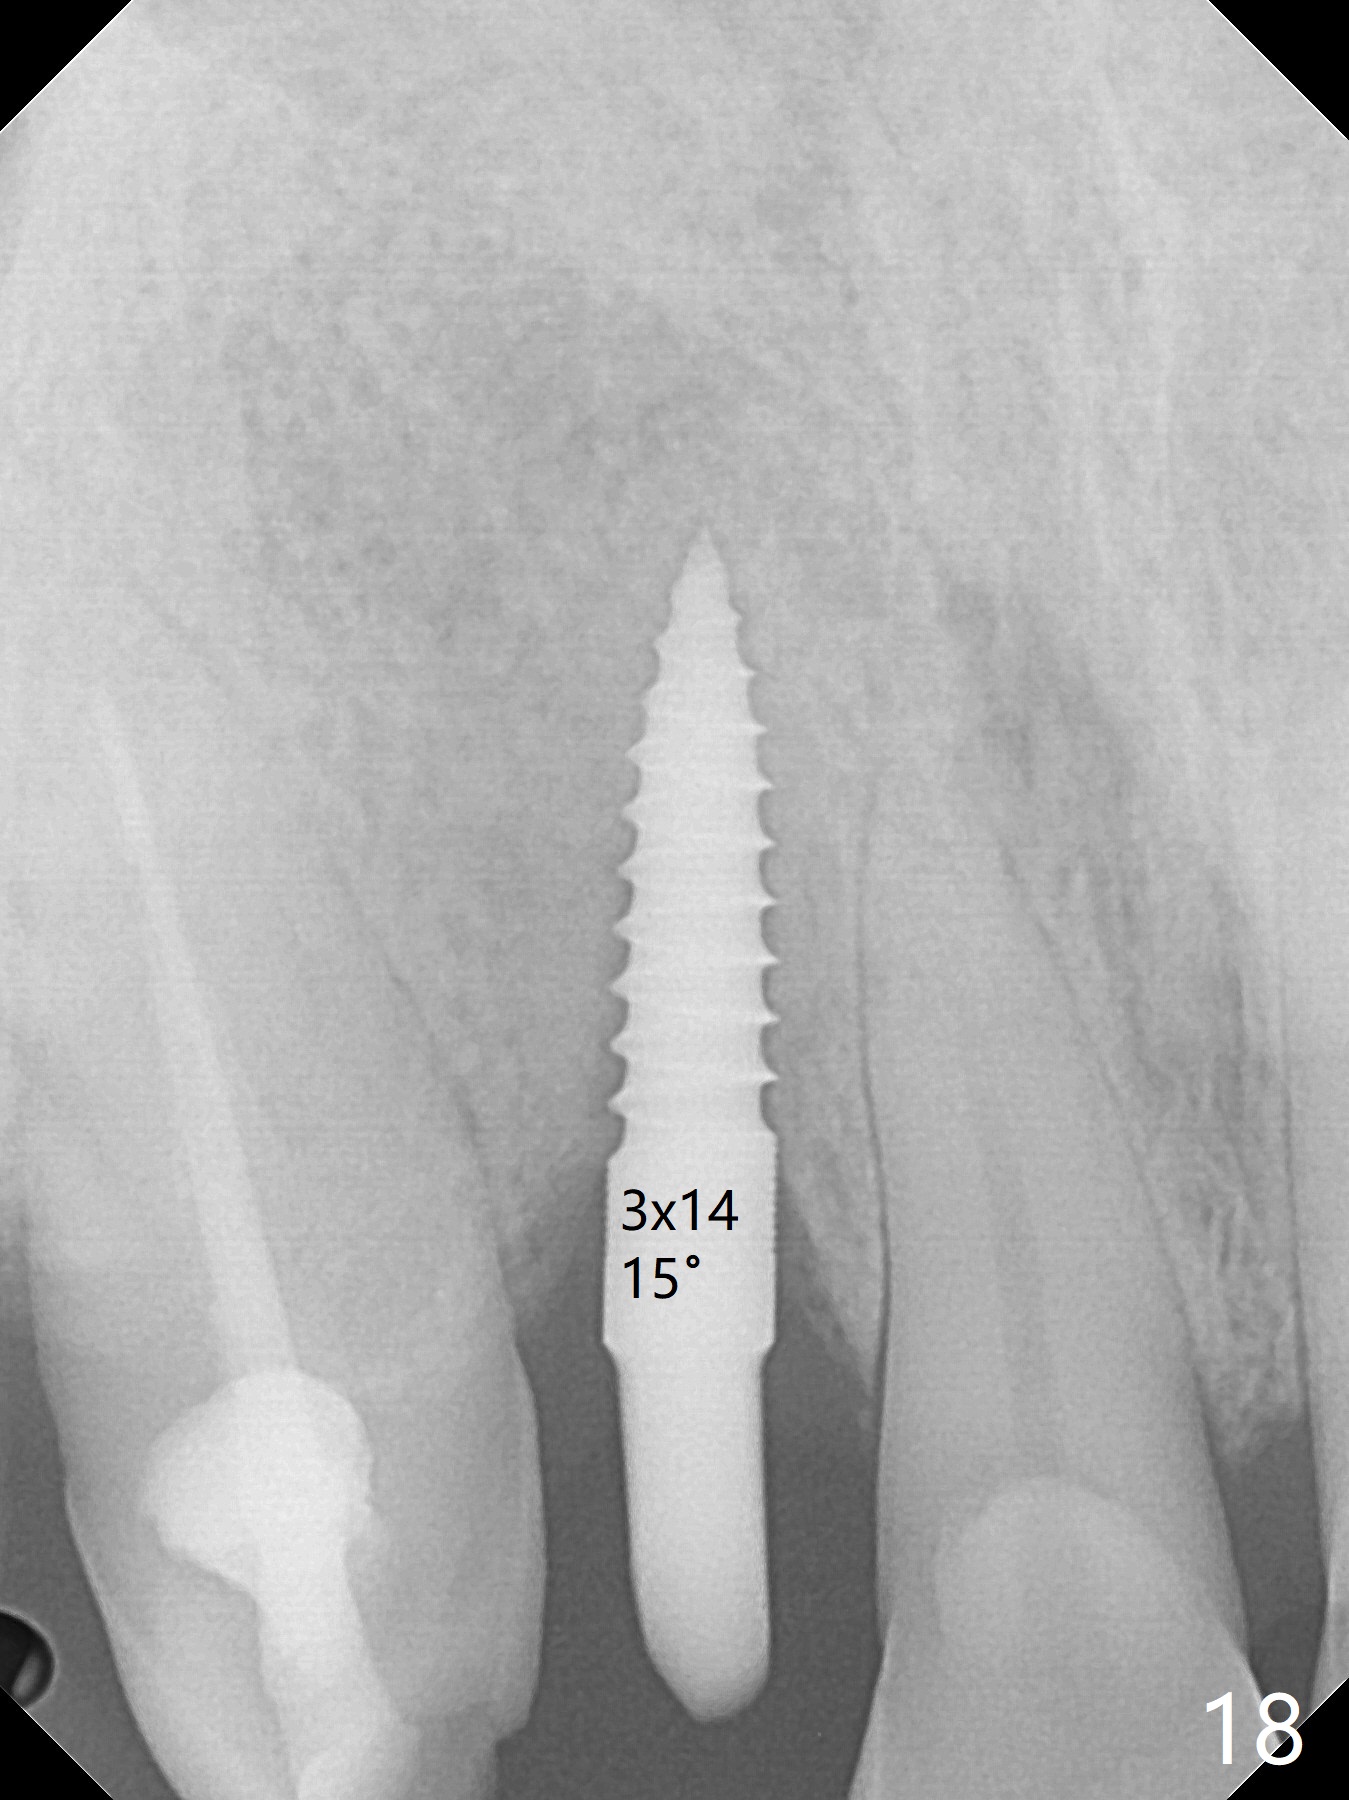

An apical abscess is present when the patient returns for immediate implant at #7 (Fig.1 *); a 2nd challenge is deep bite. After smooth extraction, the apical buccal plate is found to be perforated. Following debridement, a piece of gauze is placed in the apical defect for hemostasis, while osteotomy is initiated palatal (Fig.2). The apical defect seems to be extensive (Fig.3 yellow dashed line). A new trajectory is intended (red arrow) without much success. Before implant placement, bone graft is placed in the apical defect defect area, while a drill (Fig.4 D) is inserted in the finished osteotomy (Fig.5 O). In spite of seemingly large apical defect, the buccal crest bone exists (Fig.4 x). A 3x14(2) mm 1-piece implant is placed with stability; the first round of bone graft is apparently around the apical portion of the implant (Fig.6 *). The coronal end of the implant has to be adjusted several times buccopalatally to accommodate the deep bite. A 2nd round of bone graft following an immediate provisional closes the coronal space of the socket (Fig.7 *). CT will be taken to show the bone graft to repair the buccal plate defect when the patient returns for postop follow-up. In fact the defect is minimal in CT a month ago. The fistula does not disappear 1 week postop, but it is non tender (Fig.8). The patient complains of asymptomatic swelling in the right nostril. CT shows that the large buccal perforation is repaired with large amount of bone graft (Fig.9,10 *). It would be nicer to place the implant slightly more buccal apically (Fig.11 red lines; Fig.12 (preop design)). The buccoapical fistula disappears nearly 1 month postop (Fig.13). The apparently "lifeless" bone graft seems to be harmonious with the surrounding tissue (Fig.14). The periimplant gap reopens with implant mobility nearly 4 months postop (Fig.15), which is related to micro-movement associated with the immediate provisional. The latter is removed. A larger 2-piece implant will be placed in a 2-staged manner if needed (Fig.16). In fact the 3x14 mm straight 1-piece implant (Fig.17) has no mobility when it is retightened, but the trajectory remains buccal. Incision shows that there is no implant thread exposure. A 3x14 mm 15 degree angled 1-piece dummy implant is able to establish the correct trajectory, but there is no occlusal clearance (Fig.18). Micromovement during osteointegration may recreate loosening. Finally using Lindamann bur, the osteotomy is changed so that a 3.5x13 mm 2-piece implant does not need an angled abutment to establish occlusion (Fig.19). There is one palatal thread exposure. Allograft is placed circumferentially, followed by Human Amnion-Chorion Allograft and Collagen Plug. The wound does not heal 8 days postop (Fig.20), as related to the age (79 years old)? The wound appears to heal with a membrane on the surface (Amnion-Chorion one?) 3 weeks postop (Fig.21). The ridge looks wide 3.5 months postop (Fig.22,23). A 4.5x5.5(3) mm appears to be seated incompletely with a gap between the abutment and the implant (Fig.24<). A provisional is fabricated after heavy palatal reduction. Two months later, the provisional fractures. After repositioning the abutment with complete seating and torque (Fig.25), impression is taken. Although the buccal plate is concave, the gingiva remains healthy 10 months post cementation (Fig.26,27).